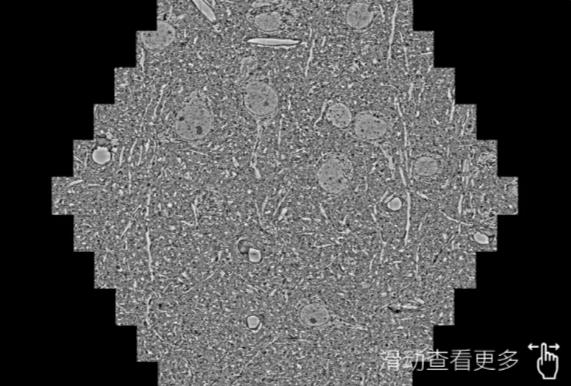

鼠脑切片。左图使用阿克苏蔡司阿克苏扫描电镜MultiSEM706对165μmx143pm面积区域成像,耗时仅需1.5秒。右图为鼠脑切片中30μm区域放大效果。样品由芝加哥大学B.Kasthuri提供。

使用蔡司高速阿克苏扫描电镜MultiSEM对1mm²人脑皮层组织进行高分辨成像,并对其中的各种细胞结构进行三维重构分析。左图展示了2x3mm²组织平面中锥体神经元的三维重构效果。右图显示了局部体积神经元三维重构。图像由哈佛大学chtman实验室提供,渲染图由D. Berger 制作。